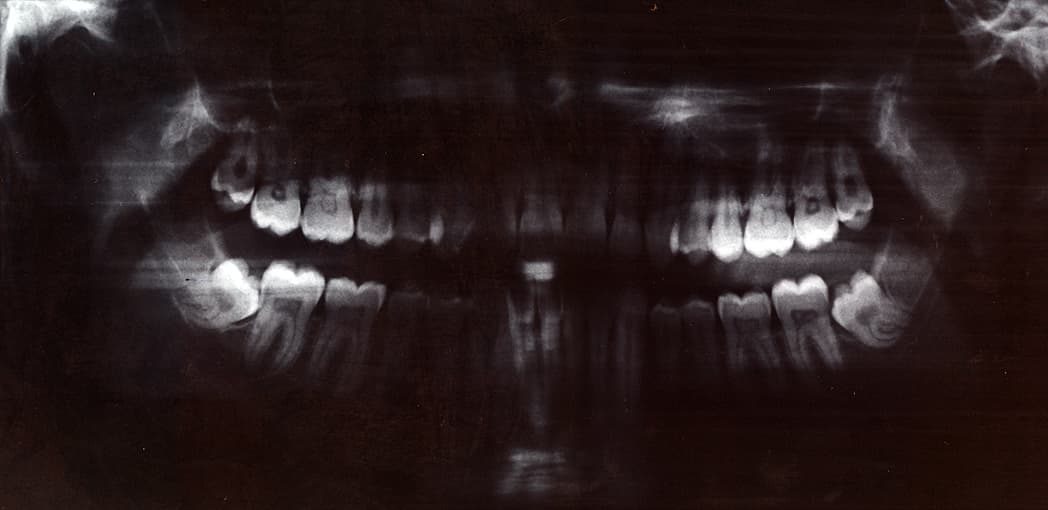

A panoramic radiograph is a panoramic scanning dental X-ray of the upper and lower jaw. It shows a two-dimensional view of a half-circle from ear to ear. Panoramic radiography is a form of focal plane tomography; thus, images of multiple planes are taken to make up the composite panoramic image, where the maxilla and mandible are in the focal trough and the structures that are superficial and deep to the trough are blurred. Other nonproprietary names for a panoramic radiograph are dental panoramic radiograph and pantomogram; Abbreviations include PAN, DPR, OPT, and OPG (the latter, based on genericizing a trade name, are often avoided in medical editing). Dental panoramic radiography equipment consists of a horizontal rotating arm which holds an X-ray source and a moving film mechanism (carrying a film) arranged at opposed extremities. The patient's skull sits between the X-ray generator and the film. The X-ray source is rectangular collimated beam. Also the height of that beam covers the mandibles and the maxilla regions. The arm moves and its movement may be described as a rotation around an instant center which shifts on a dedicated trajectory. The manufacturers propose different solutions for moving the arm, trying to maintain constant distance between the teeth to the film and generator. Also those moving solutions try to project the teeth arch as orthogonally as possible. It is impossible to select an ideal movement as the anatomy varies very much from person to person. Finally a compromise is selected by each manufacturer and results in magnification factors which vary strongly along the film (15%-30%). The patient positioning is very critical in regard to both sharpness and distortions. There are two kinds of film moving mechanisms, one using a sliding flat cassette which holds the film, and another using a rotating cylinder around which the film is wound. There are two standard sizes for dental panoramic films: 30 cm × 12 cm (12′′ × 5′′) and 30 cm x 15 cm (12′′ × 6′′).